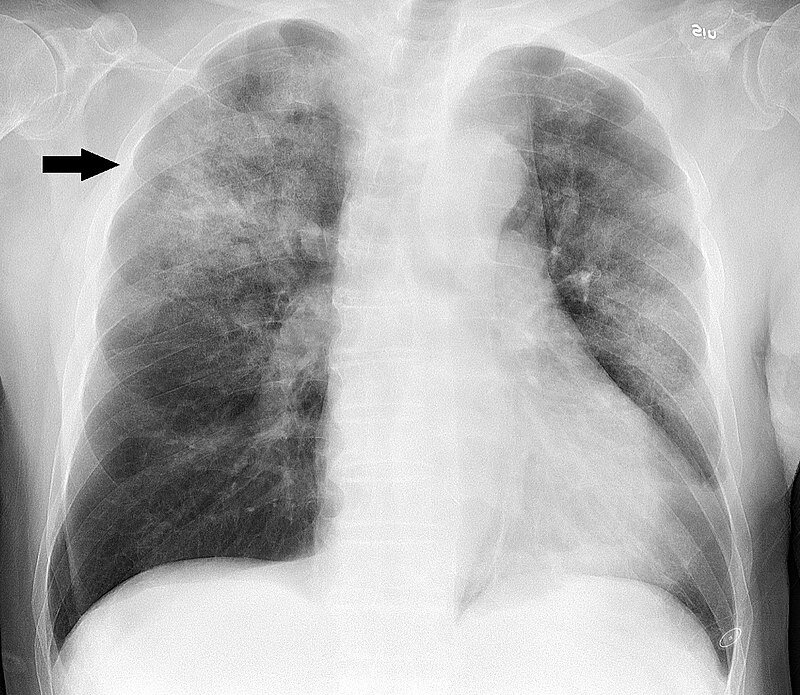

در صورت ابتلا به این عفونت تنفسی، کیسههای هوایی متورم میشود و چون درون آن از مایعات پر میشود در نتیجه، اکسیژن رسانی کمتر شده و تبادلات گازی در عروق خونی کاهش مییابد.